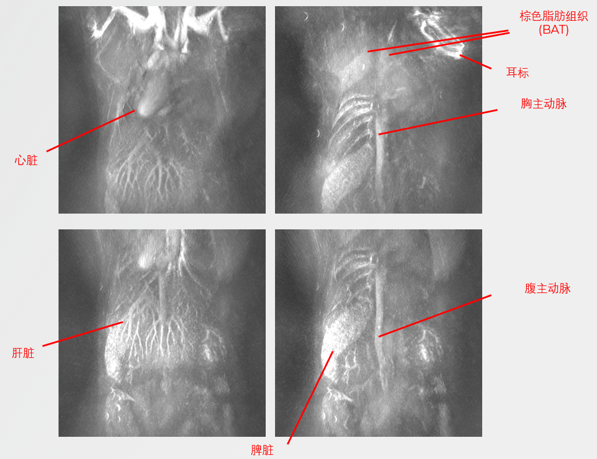

無標(biāo)記小鼠血管成像